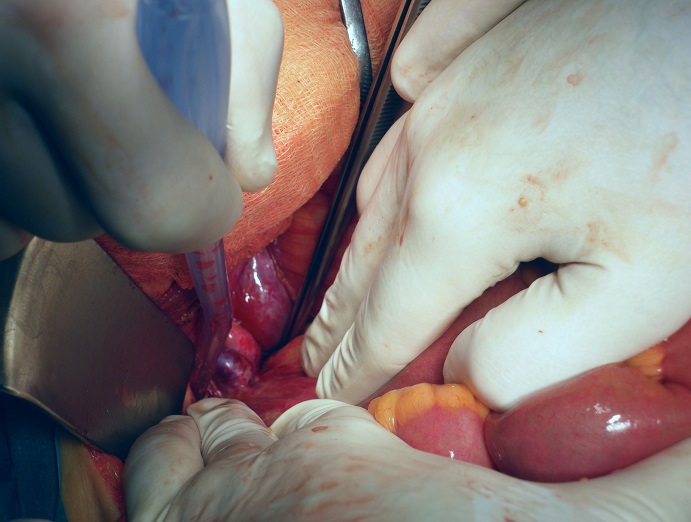

A pesar de la negatividad de las pruebas diagnósticas para localizar el punto de sangrado, la paciente continúa con rectorragia franca, anemización y necesidad de drogas vasoactivas. Se decide colocar una derivación portosistémica intrahepática transyugular (TIPS), sin mejoría del cuadro. Finalmente, al octavo día del ingreso, ante la persistencia de la hemorragia digestiva, con una necesidad de transfusión total de 17 concentrados de hematíes, 7 pool de plaquetas y 2000 mililitros de plasma, se decide laparotomía exploradora urgente. Se objetivan adherencias entre el ileon terminal y fondo uterino, una gran dilatación de venas pélvicas, así como un gran vaso venoso dilatado que se introduce en la serosa del ileon (Figura 2) y que se continúa con dilatación varicosa de vasos del mesenterio (Figura 3).

Figura 2: Gran vaso venoso dilatado que se introduce en la serosa del ileon.